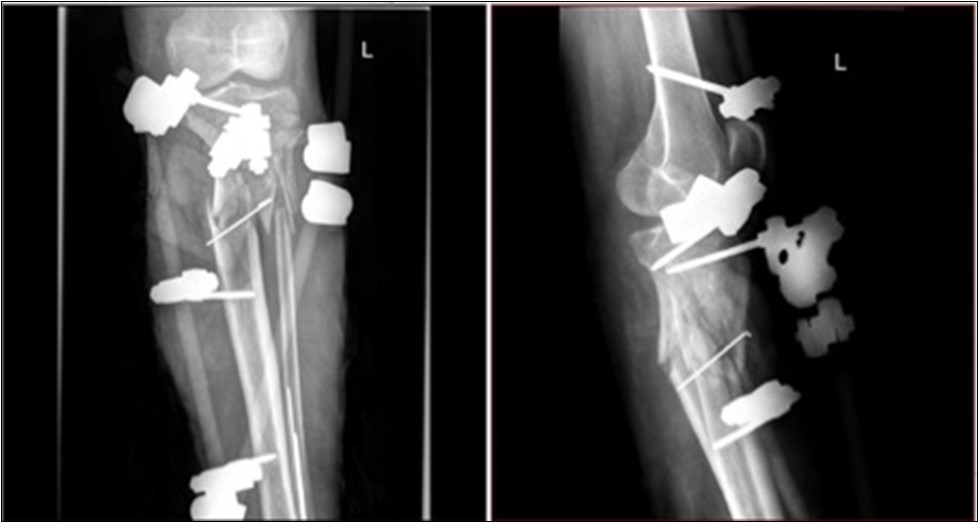

Revision of soft tissue - extensive contusolaceration of the lower limb from the Achilles tendon through the whole calf to the medial side of the thigh - circular detachment of the skin and subcutis from the fascia, macroscopic contamination.

Application of external fixation and Ki wires to stabilization of fragments.

Reconstruction of the skin cover - excision of necrotic parts, covering defects using artificial skin Synkryt. Figure 33, Figure 34, Figure 35, Figure 36, Figure 37, Figure 38, Figure 39, Figure 40, Figure 41, Figure 42, Figure 43, Figure 44, Figure 45, Figure 46, Figure 47, Figure 48, Figure 49, Figure 50.